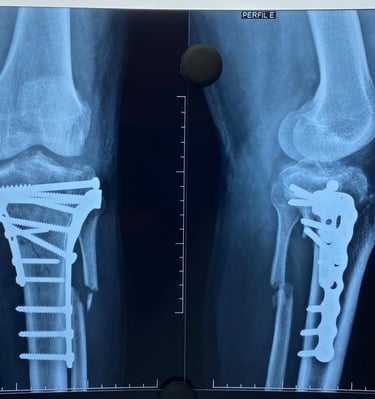

Galeria Médica

Imagens de atendimentos e procedimentos em ortopedia e traumatologia.

* Fotos autorizadas pelos pacientes para uso neste site.